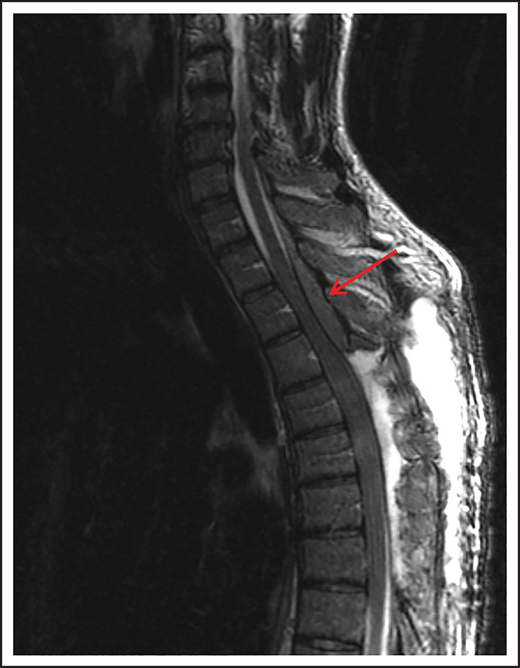

A 74-year-old man with a history of DLBCL treated with R-CHOP presented with progressive confusion and right-side weakness. A brain MRI demonstrated a contrast-enhancing lesion in the corpus callosum with extension into the left parietal region. A biopsy of the enhancing lesion confirmed a diagnosis of DLBCL. No other sites of disease were identified, and he was diagnosed with isolated CNS relapse. He was treated with HD-MTX, rituximab, and temozolomide for 4 cycles, and he achieved a complete radiographic response. Three years later, he presented with progressive memory loss, urinary incontinence, and gait ataxia. A brain MRI demonstrated periventricular white matter T2/FLAIR hyperintensities (Figure 3). Evaluation for toxic and metabolic causes of his symptoms was negative. His diagnosis was MTX-induced leukoencephalopathy.

Brain MRI of a patient with leukoencephalopathy caused by use of HD-MTX. An axial T2 fluid attenuated inversion recovery (FLAIR) image shows periventricular hyperintense signal reflecting leukoencephalopathy.

Antimetabolites

HD-MTX as well as IT MTX can cause acute as well as subacute encephalopathy.57,58 Acute encephalopathy is usually reversible. Subacute, or chronic, encephalopathy, as seen in case 4, is typically progressive, irreversible, and associated with high morbidity and mortality. It is a diagnosis of exclusion and as described in case 4, other causes must be excluded. The risk is higher with older age and when combined with whole-brain radiation therapy (WBRT).59